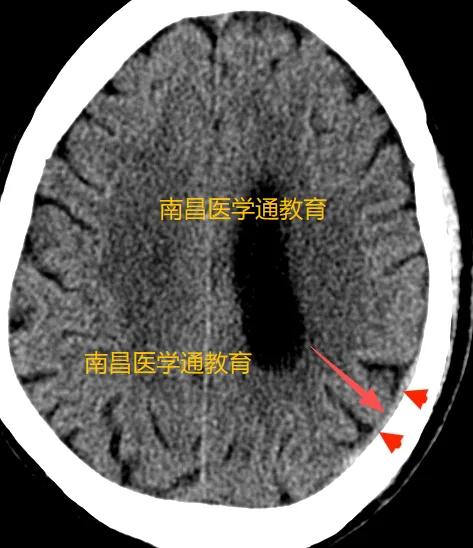

下面是窄窗宽显示的效果:

大家看是不是更好的显示了。